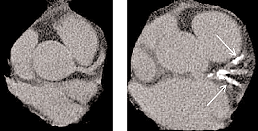

To help you better understand the connection between calcium and vascular disease look at these pictures.

The picture on the left is a normal heart, notice the relative consistency in the density of the chambers and the vessels. On the right is a diseased heart with hardened arteries. Note first the size difference, diseased hearts tend to work harder, enlarging the muscles and making it less efficient. Also notice the white spots noted by the arrows; these are the coronary arteries that supply blood flow to the heart itself. When you have a heart attack, it is these arteries that are affected.

Here is an example of calcified arteries in the brain. Hardening of the arteries can happen anywhere; in the heart as above leads to heart attacks, and examples like these in the cerebral arteries lead to strokes. Calcium shows up bright white on Xray which is why bones show up that way. Note there is very little difference between the skull bones and these cerebral arteries! So you need calcium intake, but could too much intake lead to accumulation in the wrong places? This study seems to indicate that may be the case.